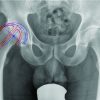

A 42-year-old man with a history of two total knee replacements (TKRs) 4 years apart presented to us with chief complaints of pain, swelling of the left knee, and inability to bear weight for 2 months. The patient had undergone a primary total left knee replacement 8 years ago (Fig. 1). Four years later, the patient sustained an aseptic failure of primary TKR, after which a revision TKRs was performed (Fig. 2). Revision was performed through the previous incision (medial parapatellar approach), and loosening of the femoral component was noted. The medial tibial bone graft was resorbed (F2B defect in both femoral condyles and T2A defect in the medial tibial condyle). In view of this, the prosthesis was explanted and a rotational knee replacement with anti-dislocation mechanism was inserted (Link-Waldemier, non-modular (rotational) joint endo-model). In this procedure, the femoral defect was reconstructed with a polyethylene spacer, and the tibial defect was reconstructed with cement. After the revision surgery, the patient was asymptomatic for 3 years. Subsequently, he began to experience episodes of instability. He presented to us 2 months after the onset of symptoms, with complaints of pain in the knee. A radiograph was obtained and a posterior dislocation of the hinge prosthesis was diagnosed (Fig. 3). The patient was taken for surgical intervention through the previous incision. When the knee joint was exposed, it was found that there was complete polyethylene wear of the anti-dislocation mechanism (Fig. 4). The fixation screw which had loosened was removed, the polyethylene insert was replaced, and a new polyethylene insert was implanted. The anti-dislocation mechanism’s wear and tear has no specific cause. An examination of the literature does point to aseptic loosening as one of the causes in our situation, although improper placement is also a possibility. Stability was confirmed intraoperatively. The post-operative period was uneventful (Fig. 5). The patient achieved a range of motion of 0–120° in the knee at 4 weeks post-operative with complete resolution of pain. The knee society score of the patient improved from 40 pre-operatively to 90 postoperatively at 1-year follow-up (Fig. 6). An explained informed consent has been taken from the patient and their legal guardian for publishing images concerning them before writing this case report.